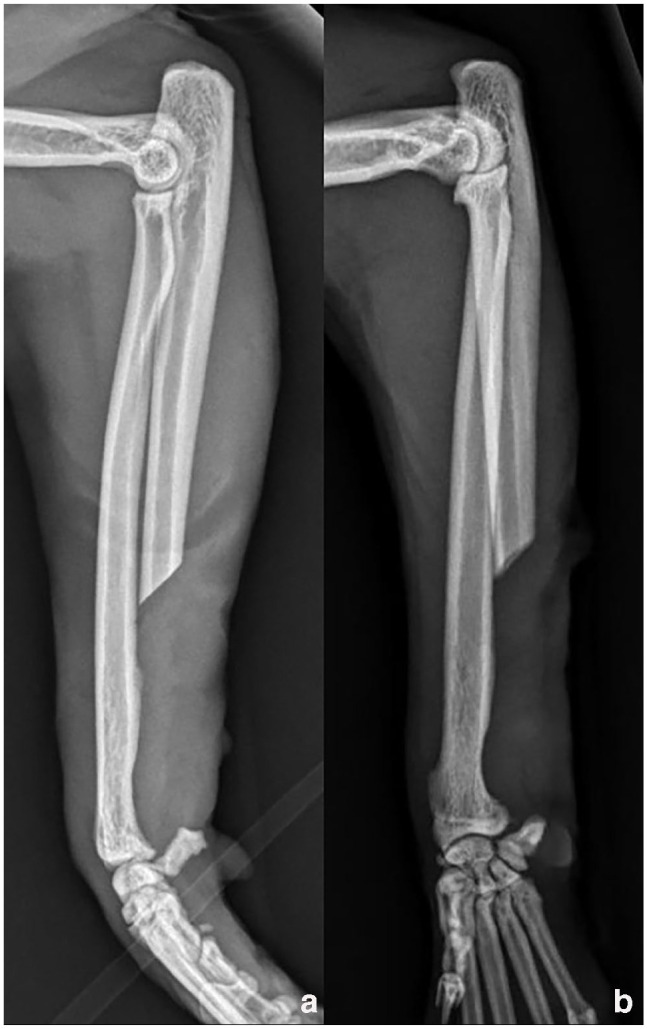

Case summary: An 8-year-old male neutered domestic shorthair cat was presented with an acute onset of left thoracic limb lameness and a firm swelling on the lateral aspect of the left distal antebrachium. A CT scan of the left thoracic limb revealed an expansile osteolytic cystic bone lesion centred at the distal left ulnar metaphysis. Cytology from fine-needle aspiration was not consistent with neoplasia. The CT features and the cytology results were suggestive of a bone cyst. A distal partial ulnectomy with ulnar styloid process excision was performed as the biopsy method and as the treatment approach. Histopathology results were consistent with an aneurysmal bone cyst (ABC). Carpal instability was not detected after distal partial ulnectomy; therefore, a stabilisation method was not required. Limb function was excellent after surgery, with no lameness and no recurrence detected by the owner at 2, 6 and 24 weeks postoperatively. The veterinary examination at 12 weeks postoperatively confirmed the owner's outcome assessment.

Relevance and novel information: To the authors' knowledge, this is the first report describing a distal partial ulnectomy with ulnar styloid process excision in a cat. Despite disrupting the short ulnar collateral ligament, this technique provided excellent short-term limb function with no need for carpal joint stabilisation. This technique allowed for the complete excision of a distal ulnar ABC and avoided cyst debridement, which could be associated with haemorrhage, recurrence and malignant transformation. Distal partial ulnectomy should be considered for distal ulnar bone lesions in cats.